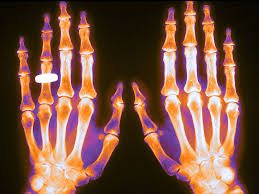

Existe controversia sobre cómo, cuándo y por qué suspender potencialmente estos agentes. Analizamos la interrupción permanente y temporal del tratamiento a largo plazo con bifosfonatos y denosumab. Nos centramos en los motivos y el momento de la interrupción, así como en las estrategias para mitigar el riesgo futuro de fracturas.  Arthritis Rheumatol,  2025

Esta es la segunda entrega de la Folia DOC  dedicada a osteoporosis. La primera se enfocó en el diagnóstico, prevención y medidas no farmacológicas, y en esta se aborda el tratamiento farmacológico. El mismo variará según el riesgo estimado de fractura, la consideración de la eficacia y seguridad de los diferentes fármacos, la conveniencia de su administración y las preferencias de las pacientes. FoliaDOC, Fundación FEMEBA, 27 de enero de 2025.

El Grupo de Trabajo sobre Cuidados Preventivos de EEUU (USPSTF) concluye con certeza moderada que la detección de osteoporosis para prevenir fracturas osteoporóticas en mujeres de 65 años o más y en aquellas mujeres postmenopáusicas menores de 65 años con un riesgo de osteoporosis aumentado,  tiene un beneficio neto moderado. (Recomendación de tipo B). También concluye que la evidencia es insuficiente para determinar el balance de beneficios y daños de la detección de osteoporosis en los varones. JAMA, 14 de enero de 2025.

El riesgo de hipocalcemia que requirió tratamiento de emergencia fue mayor con denosumab que con bifosfonatos, y aumentó con los estadios más avanzados de la enfermedad renal crónica, alcanzando el máximo en pacientes dializados. Annals of Internal Medicine, 18 de noviembre de 2024.